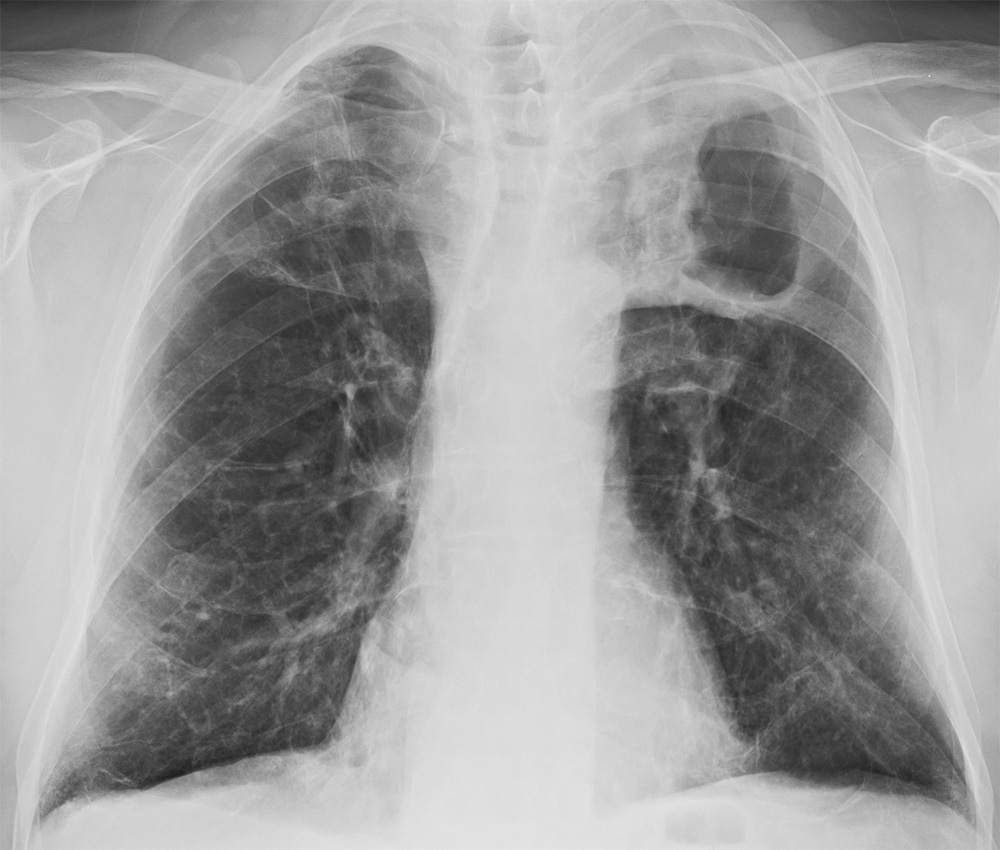

- 폐렴: 폐렴은 다른 호흡기 질환과 달리 반드시 열이 난다는 특징이 있습니다. 따라서 열과 기침이 나면서 숨이 차는 경우는 폐렴 진단을 받을 가능성이 매우 높습니다.

- 폐결핵: 수개월 동안 기침과 가래가 지속되는 것이 특징이며, 식은땀이 나거나 체중이 빠지는 등의 전신 증상이 동반되는 경우 폐결핵을 의심하고 병원에 가야 합니다. 가슴 사진을 찍어보면 바로 진단받을 수 있습니다.